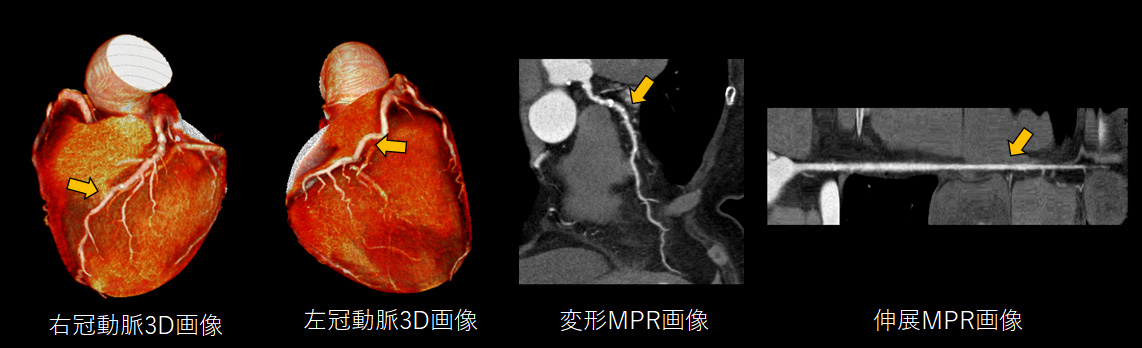

循環器領域

✓ 高速撮影の利点を活かした静止画像を作成

心臓は握りこぶし程の小さな臓器であり、その血管はさらに微細かつとどまることなく常に動き続けています。この血管を静止画像として画像化することは非常に困難なことですが、最速0.35秒で撮影が可能な当院の撮影技術を最大限に活かすことで、心臓においても他の動きのある臓器同様に動きやボケのない画像提供が可能です。心臓の血管の石灰化などを評価することで、治療に役立てます。

CT撮影後は、診療放射線技師が「MPR画像」や「3D画像」と呼ばれる高度な画像を作成することで、骨折の程度を正しく判断し、患者説明や手術の際に役立てています。